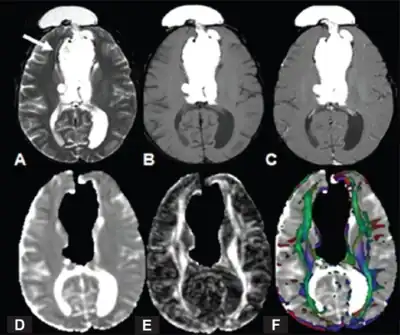

MRI -a) Interhemispheric hyperintense mass arrow T2W b) and T1W c) post-contrast T1W image d) hypointensity in lesion e) FA f) color-coded FA indicate agenesis of corpus callosum

Callosal disorders can be diagnosed through brain imaging studies or during autopsy.[6] They may be diagnosed through an MRI, CT scan, Sonography, prenatal ultrasound, or prenatal MRI.[1]